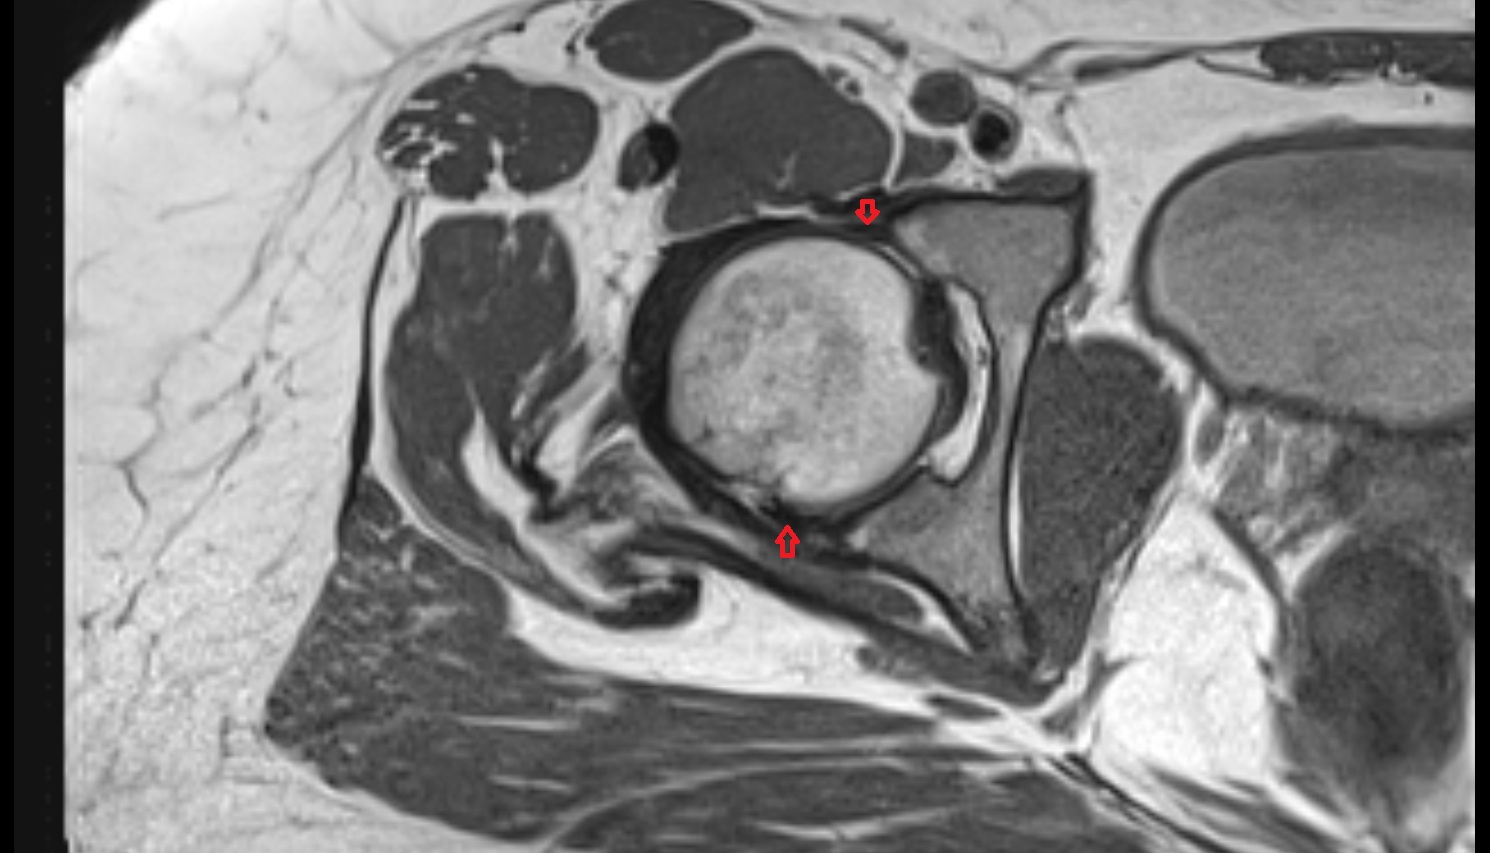

- Head of femur

- Acetabulum

- Acetabular labrum

- Articular capsule of hip joint

- Hip joint